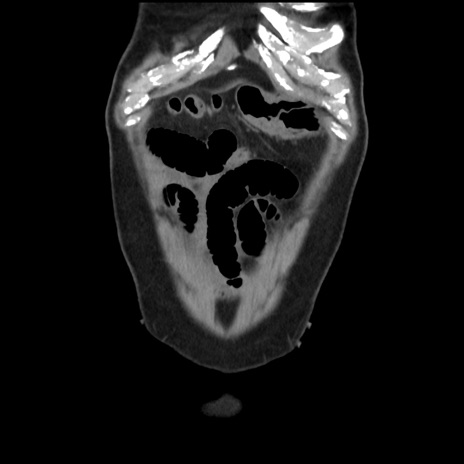

横断像